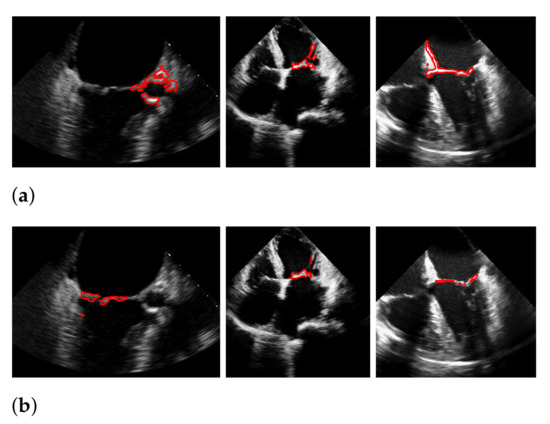

5.5. Results on the EchoNet-Dynamic Dataset